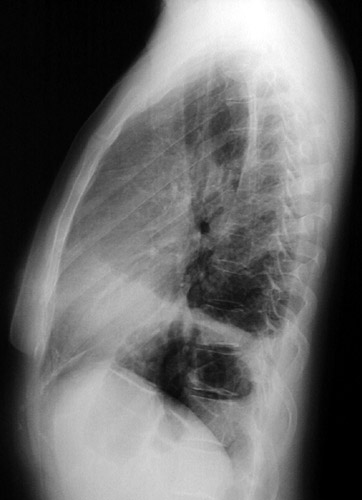

In the PA view of a chest radiograph ahove, there is a large anterior mediastinal mass which proved to be Hodgkin's disease. There is also an elevated left hemidiaphragm from left phrenic nerve invasion by the mass. The lateral view is seen below.